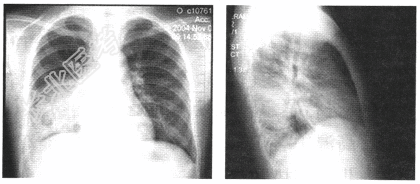

- 单项选择题患儿,女, 6岁。咳嗽发热3天,体温39℃, X线胸片如图,目前该患者最可能诊断为( )。

A、右肺细菌性炎症

B、右侧胸腔积液

C、右肺脓肿

D、右肺结核

E、肝脓肿